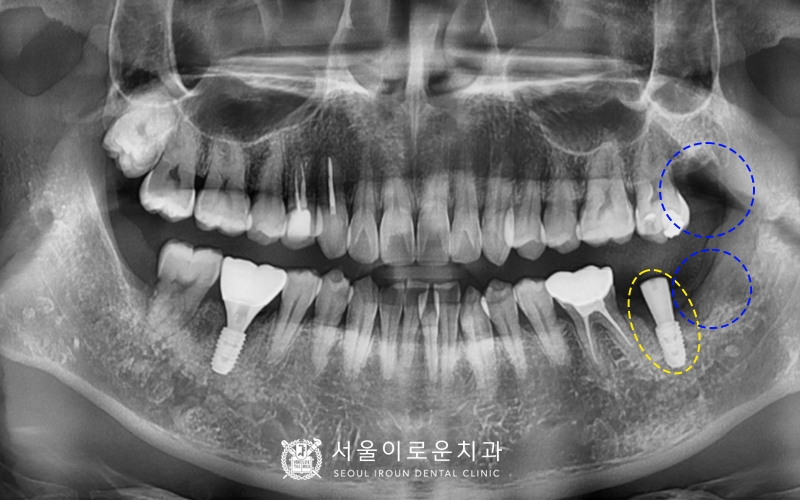

부천서울이로운치과를 찾아주신 40대

남성분의 파노라마 사진입니다.

특징적으로 눈에 띄는 것은

아래 양쪽 어금니 두개가 파절되어

부러져있는 것이었는데요.

왼쪽 아래 두번째 큰어금니(#37)는

뿌리만 남아있어 발치가 필요한 상황이었고,

오른쪽 아래 첫번째 큰 어금니(#46)는

과거 신경치료 후 크라운을 하지 않아

충치가 진행되어 이가 부러진 상태로

발치 후 뼈이식을 동반한 임플란트를

계획하기로 하였습니다~!